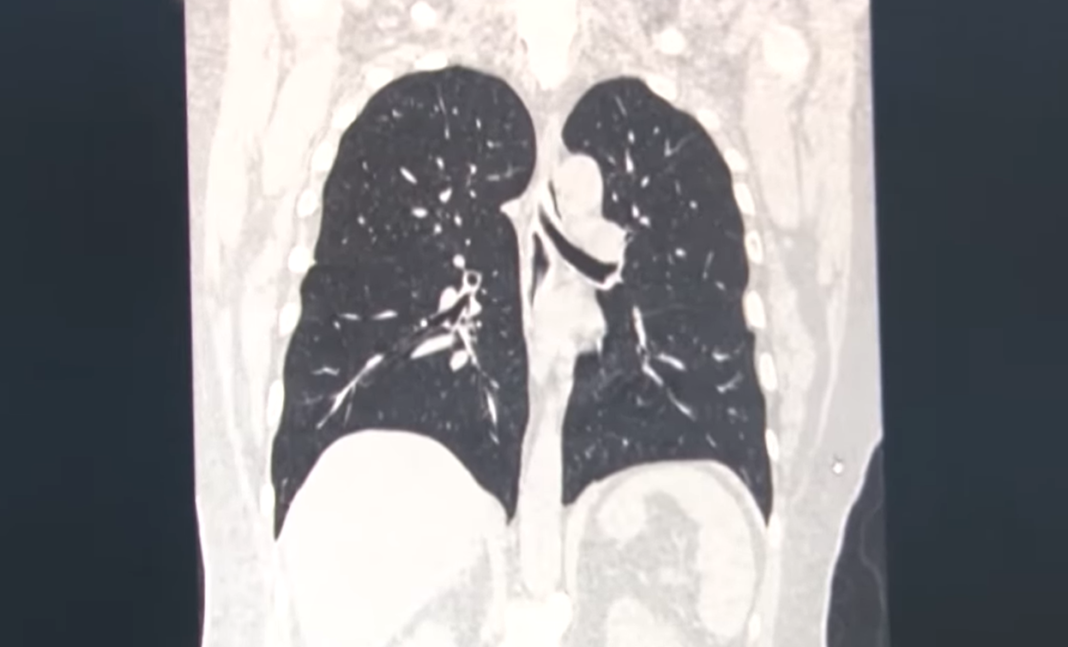

sursa foto: captură facebook/Spitalul Victor Babeș Timișoara

„Am observat o diferență însemnată, din punct de vedere imagistic, între plămânii unui pacient vaccinat împotriva SARS-CoV-2 și cei ai unui pacient nevaccinat. La peste 95 la sută dintre persoanele vaccinate, care fac totuși o infecție COVID-19, nu există o afectare pulmonară, în timp ce în cazul bolnavilor nevaccinați începe de la 30-40 la sută și poate crește, într-un interval extrem de scurt, uneori chiar și de câteva ore, până la 70-80, și chiar 85 la sută”, a spus Șef lucr. dr. Diana Manolescu.